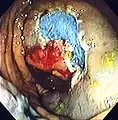

During colonoscopies when a polyp is removed (a polypectomy), the complication risk is higher.[41][42]One of the most serious complications is postpolypectomy coagulation syndrome, occurring in 1 in 1000 procedures.[43] It results from a burn injury to the wall of the colon causing abdominal pain, fever, elevated white blood cell count and elevated serum C-reactive protein. Treatment consists of intravenous fluids, antibiotics, and avoiding oral intake of food, water, etc. until symptoms improve. Risk factors include right colon polypectomy, large polyp size (>2 cm), non-polypoid lesions (laterally spreading lesions), and hypertension.[44]

The first step is usually a digital rectal examination (DRE), to examine the tone of the anal sphincter and to determine if preparation has been adequate. A DRE is also useful in detecting anal neoplasms and the clinician may note issues with the prostate gland in men undergoing this procedure.[55] The endoscope is then passed through the anus up the rectum, the colon (sigmoid, descending, transverse and ascending colon, the cecum), and ultimately the terminal ileum. The endoscope has a movable tip and multiple channels for instrumentation, air, suction and light. The bowel is occasionally insufflated with air to maximize visibility (a procedure that gives the patient the false sensation of needing to take a bowel movement). Biopsies are frequently taken for histology. Additionally in a procedure known as chromoendoscopy, a contrast-dye (such as indigo carmine) may be sprayed through the endoscope onto the bowel wall to help visualize any abnormalities in the mucosal morphology. A Cochrane review updated in 2016 found strong evidence that chromoscopy enhances the detection of cancerous tumors in the colon and rectum.[56]